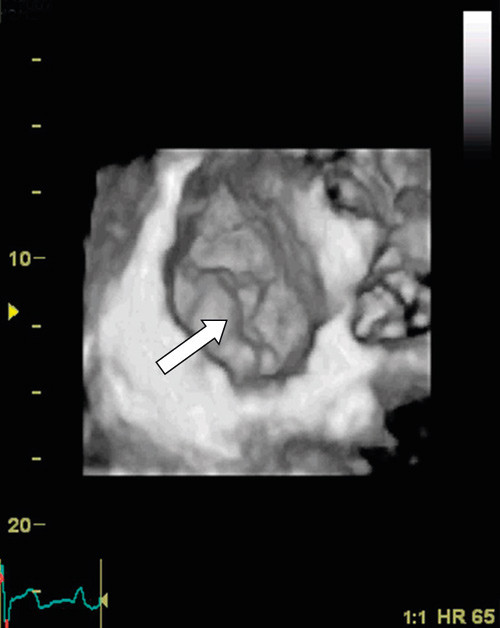

Vurdering av klaffesykdom med bruk av 3D-ekko har vært validert i ulike studier. Foreløpig er det diagnostikk av patologiske mitralklaffer som er best dokumentert (9) – (12). Det har i løpet av de siste ti år foregått en endring i den kirurgiske behandling av mitralklaffsykdom. Nye kirurgiske teknikker har muliggjort reparasjon av mitralfeilen hos mange pasienter som før måtte ha klaffeerstatning. Slik reparativ kirurgi stiller strenge krav til presis diagnostikk av mitralklaffens form og funksjon, slik at riktig kirurgisk metode kan anvendes. Pasienter med mitralklafflekkasje utredes hos oss med 3D-ekko for nøyaktig lokalisering av klaffens skade (fig 2). Vi har spesiell nytte av det såkalte kirurgiske innsyn (surgeons view) fra venstre atrium, hvor hele mitralklaffen kan fremstilles i samme bilde som vist i figur 2.

I dag er todimensjonal transoesophagusekkokardiografi påkrevd før kirurgisk teknikk velges ved behandling av mitralprolaps. Interessant nok er det nylig vist at tredimensjonal utvendig ekkokardiografi (transtorakal) var likeverdig med todimensjonal transoesophagusekkografi i lokalisering av mitralklaffprolaps (10). Tredimensjonal transoesophagusekkografi var enda mer presist i diagnostikken av kommisurale prolapser, som kan være vanskelige å reparere. Dette er viktig informasjon for planlegging av kirurgisk metode ved valg av ventil versus klaffebevarende, reparativ kirurgi. Ved en rekke hjertekirurgiske sentre i Europa gjøres det nå rutinemessig 3D-ekko før mitralklaffplastikk.